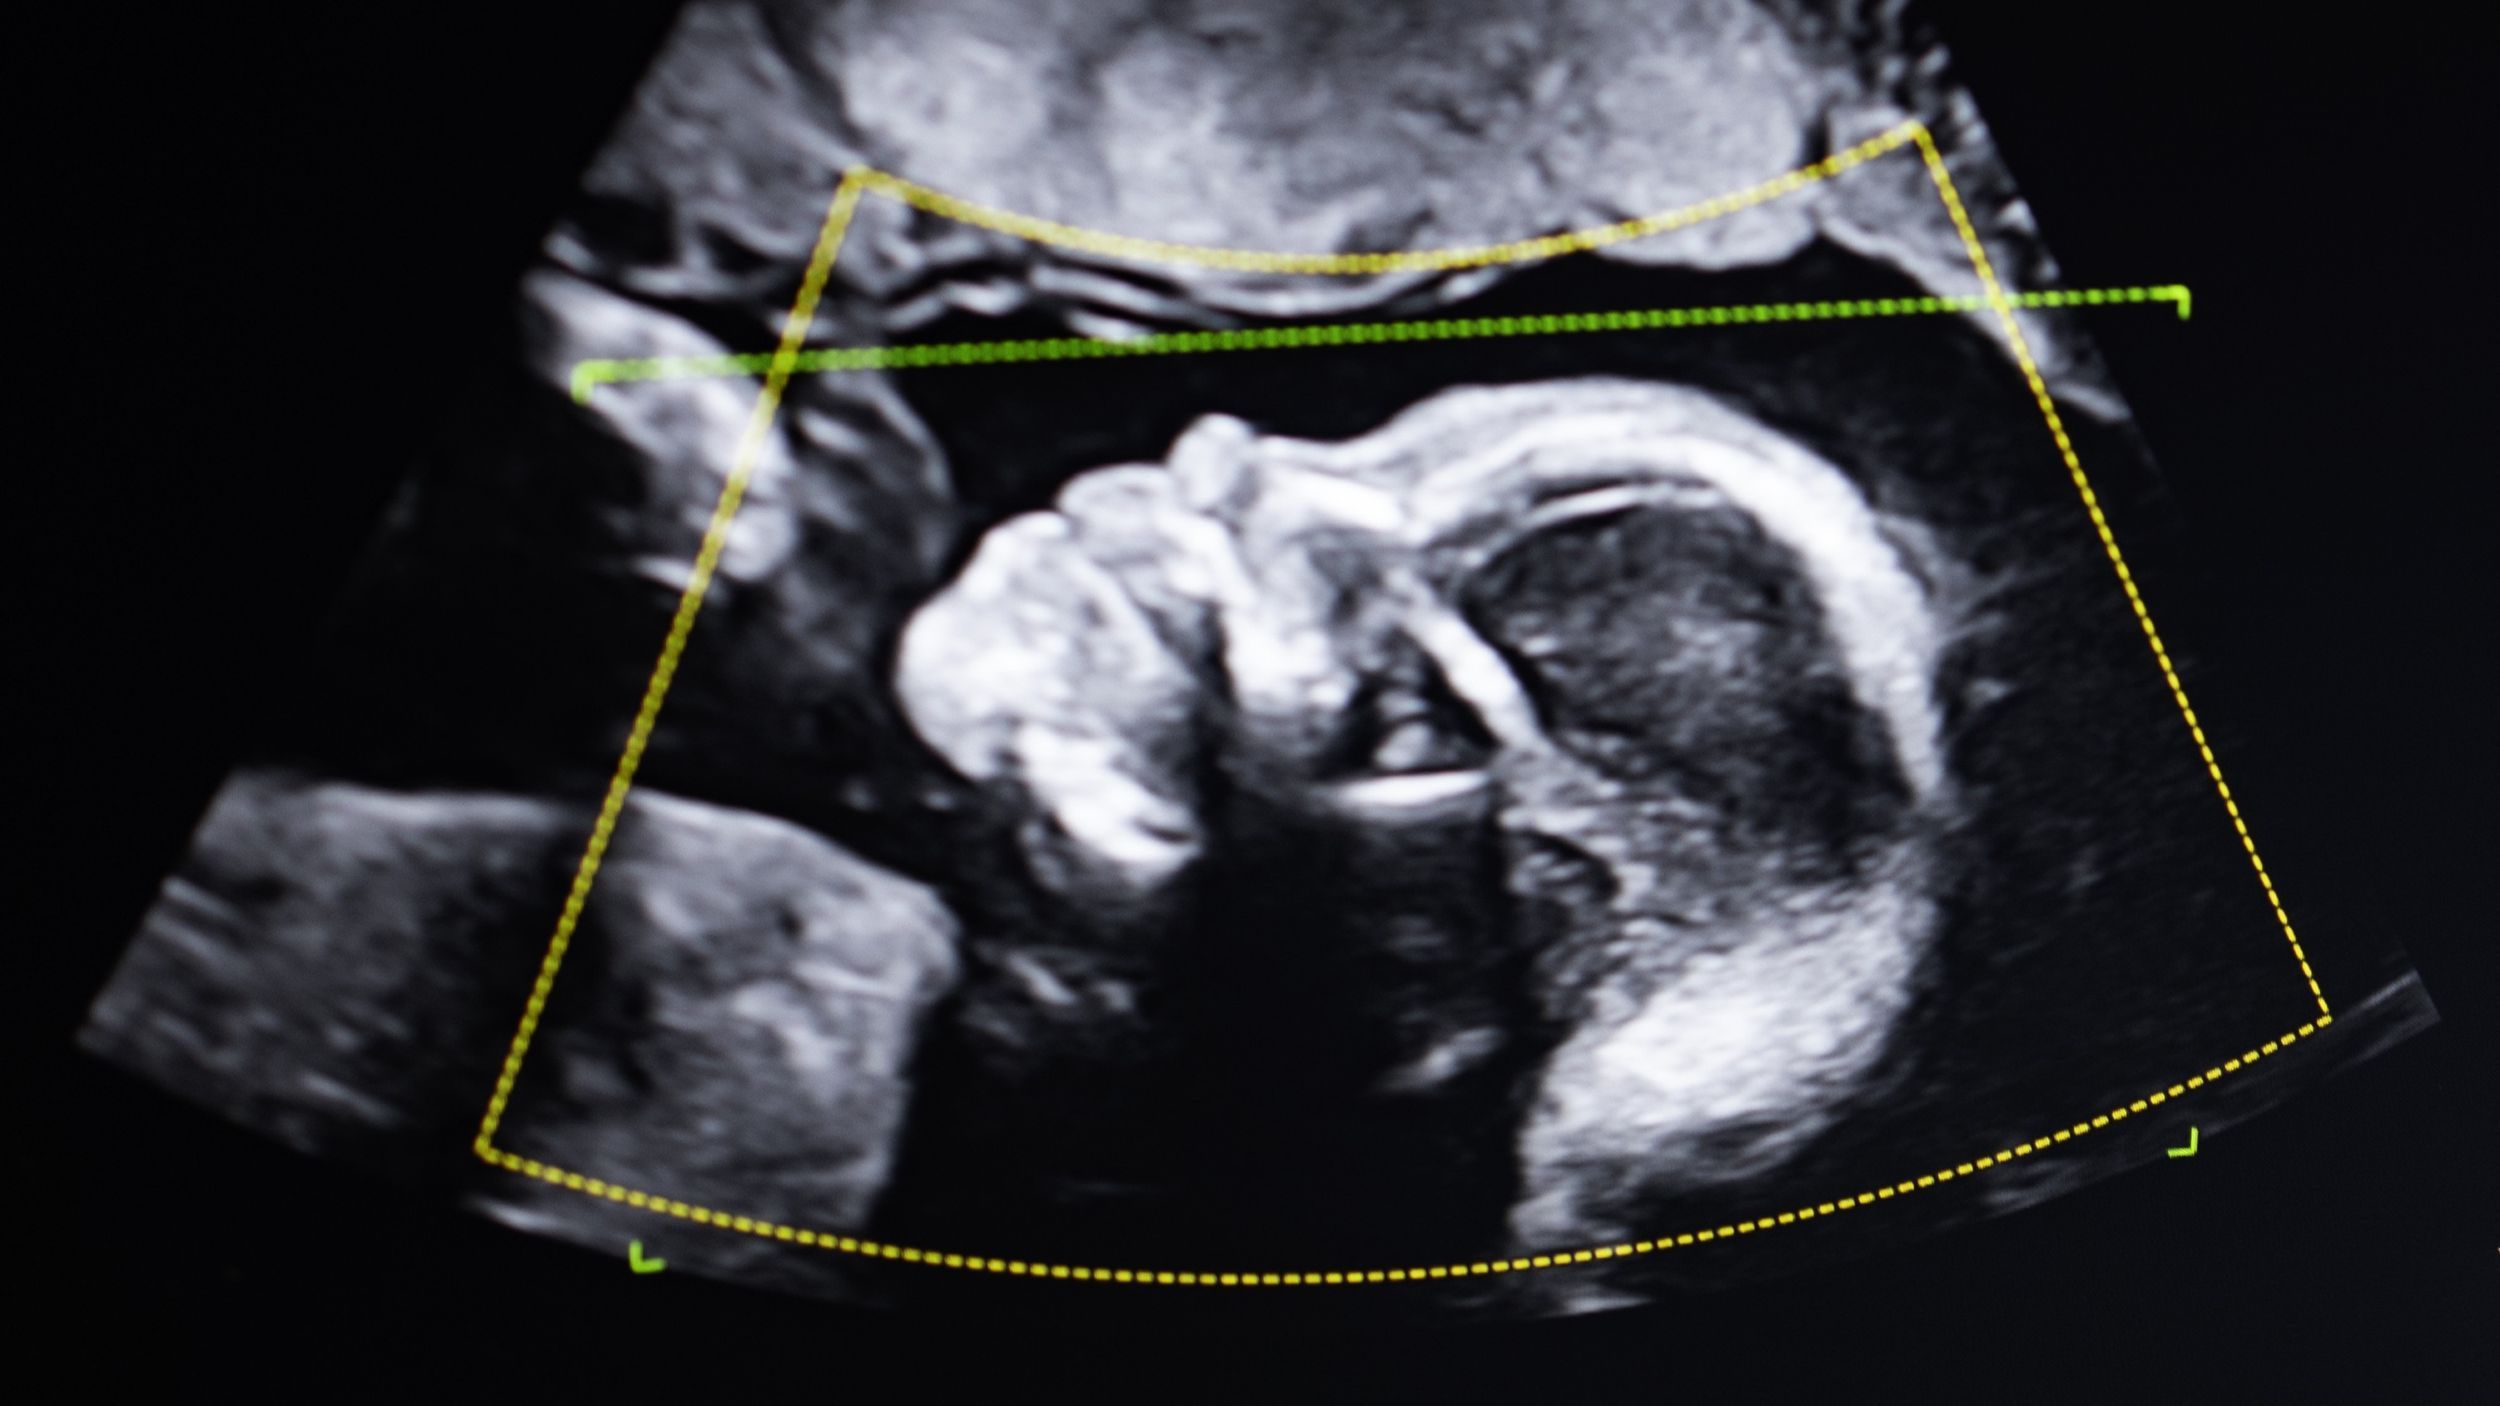

Fairchild était alors enceinte de son troisième enfant et le juge a demandé que la mère et l’enfant soient testés immédiatement après la naissance. Et l’impossible s’est produit : le troisième enfant de Fairchild, tout juste sorti de son ventre, n’était pas non plus son fils – génétiquement parlant.